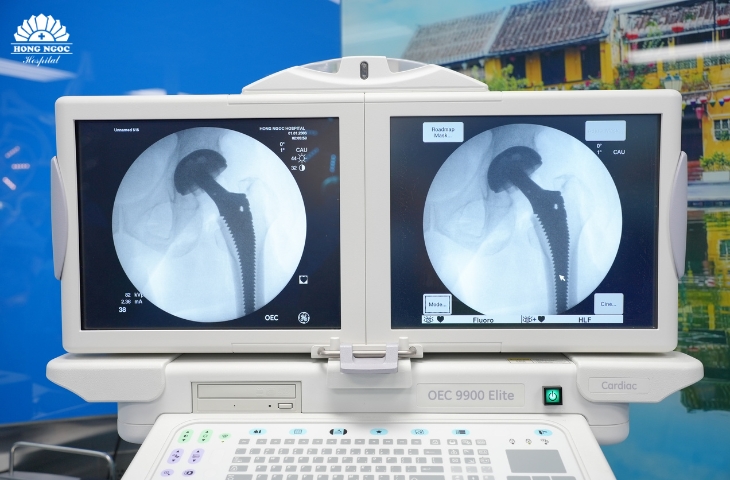

thay khớp háng toàn phần Thay khớp háng toàn phần tại Bệnh viện Đa khoa Hồng Ngọc.